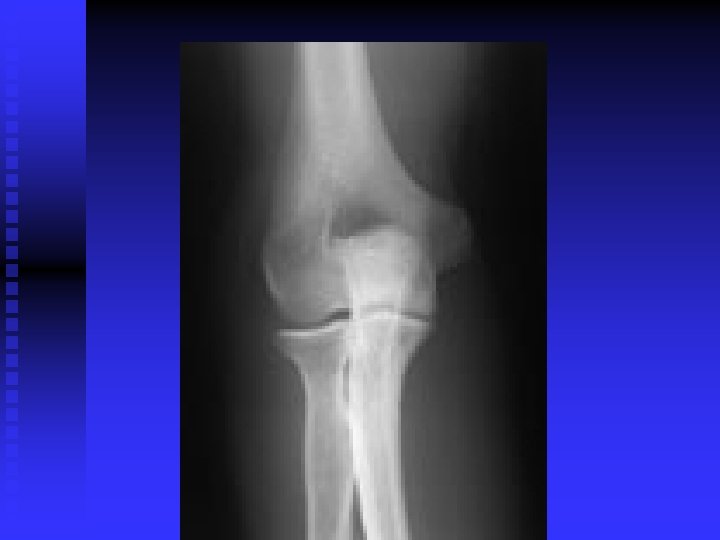

Elbow

Lateral Epicondylitis (tennis elbow) n Pathology u 30 – 50 years old u Repetitive micro-trauma u Chronic tear in the origin of the extensor carpi radialis brevis

Lateral Epicondylitis (tennis elbow) n Mechanism of Injury u Overuse syndrome caused by repeated forceful wrist and finger movements u Tennis players u Prolonged and rapid activities

Lateral Epicondylitis (tennis elbow) n Clinical Signs and Symptoms u Increased pain around lateral epicondyle u Tenderness in palpation CET u Tests t AROM; PROM t Resisted tests t Lidocaine